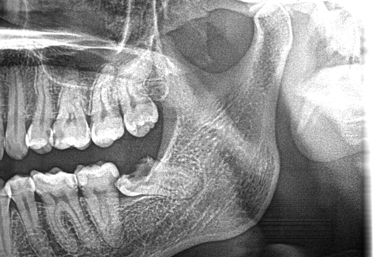

Jaw Cysts & Tumours

Expert surgical care for jaw cysts and tumours, with a strong emphasis on precision, safety, and comprehensive treatment planning.